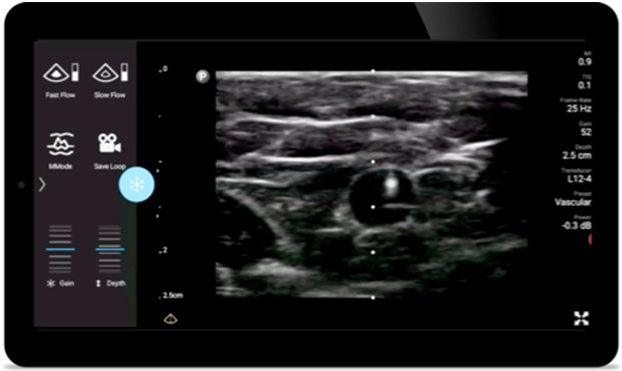

Reduce complications

in needle guided procedures

Lumify handheld ultrasound for anesthesiology helps you clearly visualize border definition with your needle placement, surrounding nerves, vessels and fascial planes.

Lumify helps you clearly visualize needle placement, surrounding nerves, vessels and fascial planes.

Broadband linear array transducer

Lumify L12-4 broadband linear array transducer

• 12 to 4 MHz extended operating frequency range

• Aperture size: 34mm

• 2D, steerable color Doppler, M-mode, advancedXRES and multivariate harmonic imaging, SonoCT

• High resolution imaging for shallow applications: soft tissue, vascular, superficial, musculoskeletal and lung

• Center line marker

• USB-C transducer with replaceable cable